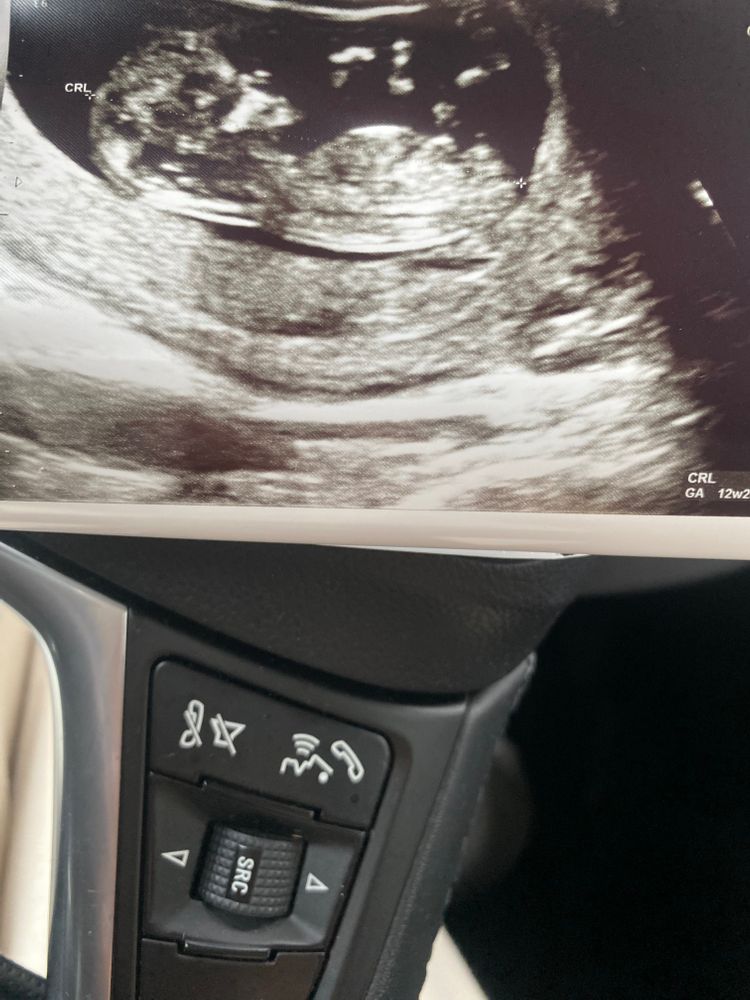

12 недель пол ребенка кого видно 🥰 как часто ошибаются?

Аня, у вас прям видно :) ну мы вчера делали и был 12.6 недель.

Если придраться, и на одной фотке подумать, что это половой бугорок - то девочка. Качество аппарата конечно.....

Жанна, качество да 🙈 хотим девочку ✨ но конечно главное здоровье.

Anastasia, ну вот плохо видно половой бугорок, к сожалению( ну сходите недель в 15-16 и точно узнаете))))

Женя, предположили мальчика 🙈

Anastasia, я вижу небольшой градус подъёма, просто на узи под разными углами смотрят и видно лучше поднят бугорок или нет) У моего сына на узи в 13 недель бугорок прямо наверх уже торчал, там было все понятно, а в 11+4 недель было как у Вас)